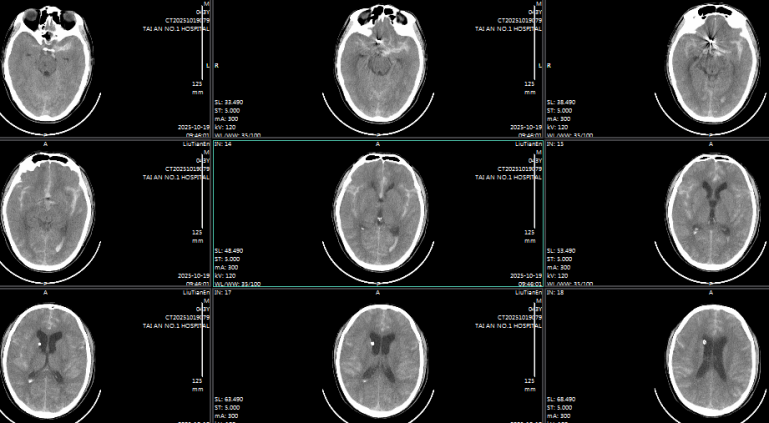

43岁的男性患者,被人发现 “肢体活动不灵、头痛伴呕吐 1 小时许” 后紧急送医,颅脑CT显示蛛网膜下腔出血并破入脑室,CTA 提示前交通动脉瘤可能性极大。术中证实,该动脉瘤大小约 4.5mm×3.5mm,瘤颈3.0mm,瘤顶指向右前方,且瘤顶可见一枚约 3.7mm×2.0mm的子瘤,同时因脑室内积血较多,还面临交通性脑积水的高风险。

针对不同患者的动脉瘤特点,团队制定个性化手术方案:74岁患者的小脑后下动脉动脉瘤体积较小,手术历时 60 分钟顺利完成栓塞;63岁患者的双动脉瘤情况复杂,尤其是较大瘤体累及血管分支,手术难度更高,团队耗时100分钟成功实现两处动脉瘤的致密栓塞;43岁患者除动脉瘤栓塞外,因脑室内积血较多,术后紧急行 “脑室钻孔引流术” 释放血性脑脊液,降低脑积水风险,整个救治过程无缝衔接。